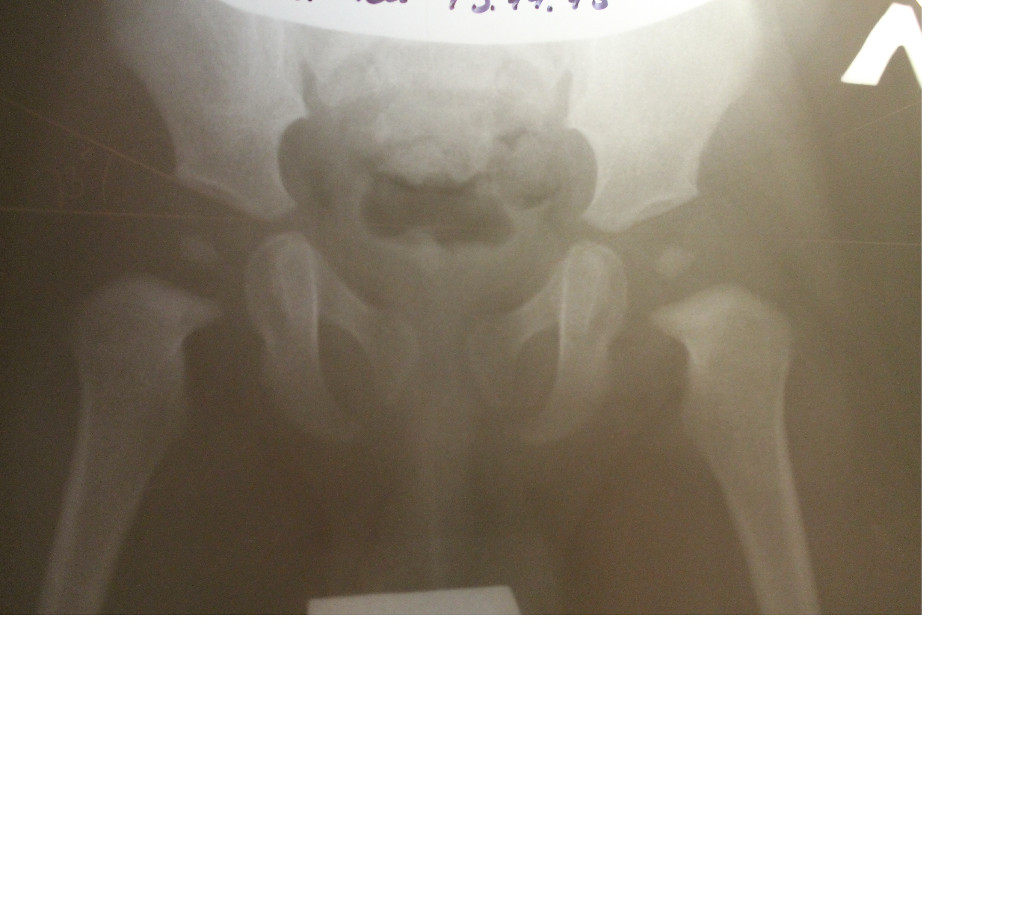

Здравствуйте, моему ребенку 10 месяцев. В шесть месяцев ортопед отправил нас на рентген тазобедренных суставов, т к заподозрил у нас дисплазию. Снимок показал следующее: ацетабулярный угол слева 26 градусов, справа 23. Дугообразная линия Шентона не изменена с обеих сторон. Ядра окостенения отсутствуют. Ортопед назначил нам электрофарез и массаж по 10 сеансов. Мы пришли на прием спустя 4 месяца, ребенку уже 10 мес. Рентген показал следующее - ацетабулярный угол слева 27 градусов, справа 23. Дугообразная линия Шентона не изменена с обеих сторон. Ядра окостенения D=S=7 мм, центрированы. Скажите такие показатели говорят о дисплазии?

Беспокоиться нет причины, на рентгенограмме возрастной вариант нормы